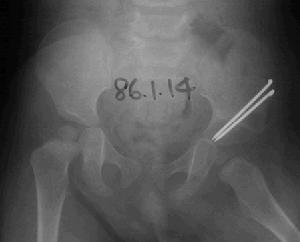

月骨脫位--影像3、併發症

月骨脫位--CT月骨周圍脫位者,月骨留在原位,其他腕骨向背側移位,並向橈側變位形成畸形。X線正位片顯示,脫位的月骨呈三角形(正常月骨應為四方形)。且投影與頭狀骨下端重疊。側位像顯示,月骨脫向掌側,半月形凹面也轉向掌側。

月骨脫位--檢查(1)X線正位片:可見腕骨排列紊亂,頭狀骨與月骨影重疊,舟月間隙增大,舟骨長軸變短,呈皮質環征或舟骨鏇轉,月骨脫位失去四邊形結構,呈三角形影。

(2)X線側位片:出現月骨周圍背側脫位,第3掌骨、頭狀骨與月骨、橈骨失去正常共軸線關係,第3掌骨及頭狀骨的軸線位於月骨及橈骨軸線背側,在此基礎上當月骨向掌側傾斜時,提示為動態性月骨周圍背側脫位,月骨掌側脫位時可見第3掌骨、頭狀骨、橈骨共軸承關係不變,而月骨位於以上諸骨軸線掌側。

月骨脫位X線正位片可見月骨輪廓,由梯形變為三角形。周圍關節間隙不平行或寬窄不等,側位見月骨掌側脫位輕者,月骨仍位於橈骨遠端凹面內,掌屈過度,橈月關節背側間隙變寬,頭狀骨與月骨背側面相對重者,月骨掌屈大於90°進入腕管內與橈骨遠端、頭狀骨完全分離。月骨周圍脫位與月骨脫位X線片影像雖然顯著,但漏診率至今仍居高不下。恐怕與X線側位片骨影相互重疊,單一腕骨輪廓難於分辨有關。診斷困難者可做CT檢查。

月骨脫位--X片2、診斷說明

根據X線片檢查不僅可以明確診斷,尚可對脫位類型進行分類。正常時腕關節正位片上月骨呈四方形,位於橈骨與頭狀骨之間,在側位片上頭骨、月骨、橈骨三者呈直線關係排列,上述關係的異常很易在X線上發覺,因此診斷並不困難。